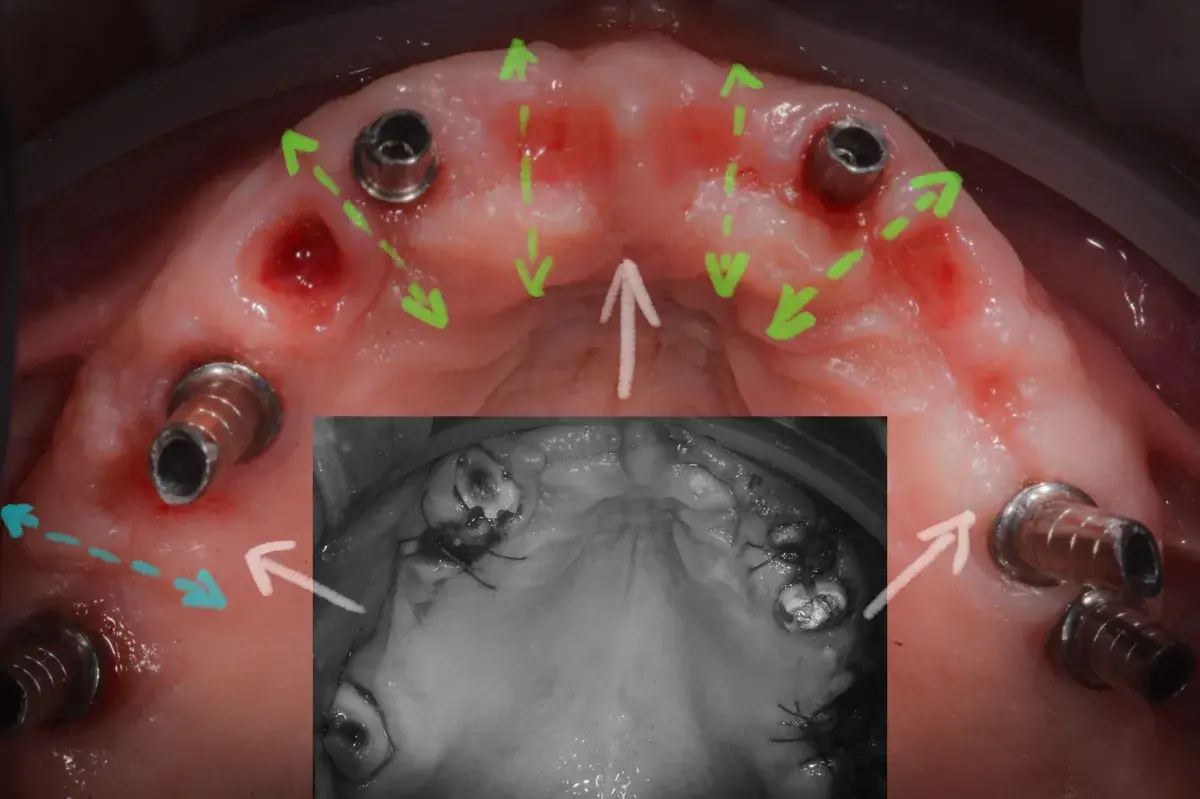

Paper 2024 su Gingival Open-Wound Technique: "innovazione" o riscoperta? Dr. Bruschi documenta guarigione per seconda intenzione nell'implantologia da...

Scopri come il tuo corpo guarisce naturalmente senza suture. La guarigione per seconda intenzione: il processo che rigenera osso e tessuti per impianti ...

Tecniche di sutura e gestione della gengiva cheratinizzata attorno agli impianti. Perché la qualità dei tessuti molli è cruciale per la longevità implan...